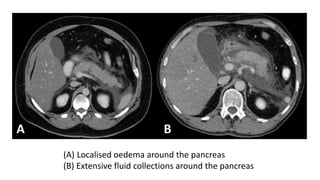

(A) Localised oedema around the pancreas

(B) Extensive fluid collections around the pancreas